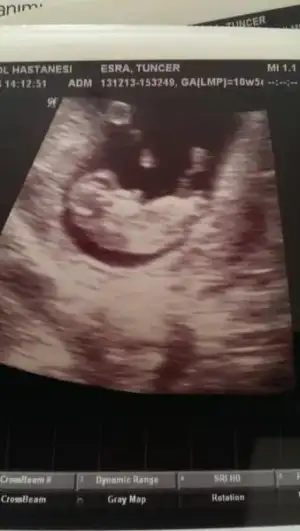

:)) aynı bende düşünmedim değil :):) eweya çok güzeldi $1598164_585696058171818_858496683_n.webp buda benim pinokyom :):)